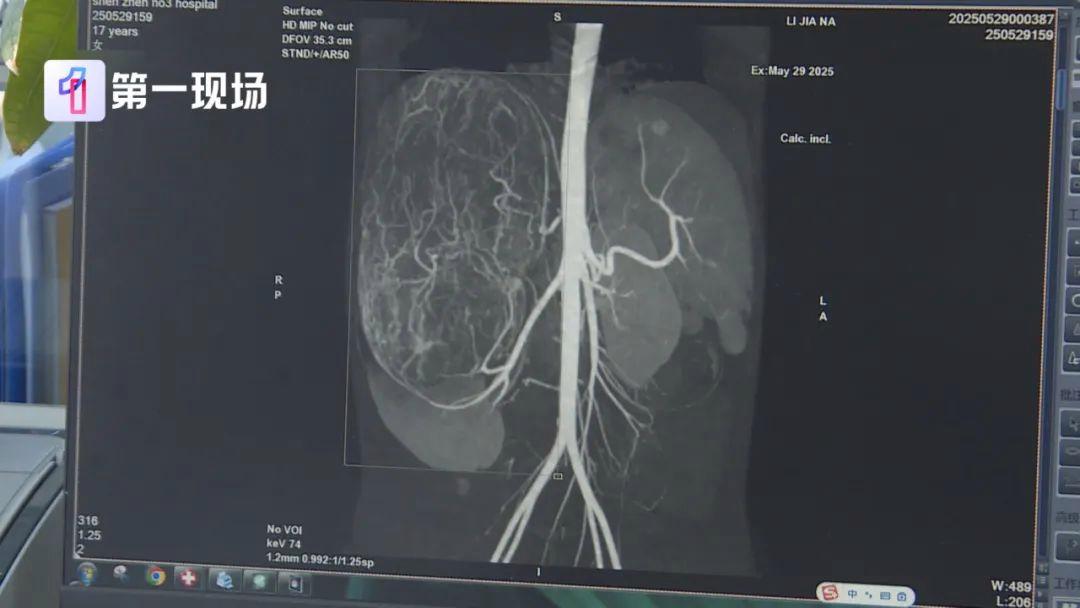

等到了当地医院一检查,CT结果显示,她的右肾有恶性肿瘤伴肝转移可能,家长就立即带着孩子来到深圳求医。

肿瘤已经到了肚脐的下缘,就是后腹直肌外侧,这种情况需安全地把肿瘤切除,不要把肿瘤搞破,是我们首先要考虑的问题。

肿瘤切出来后,我们测量了大小有27公分,重量有2.435公斤,非常非常的大。